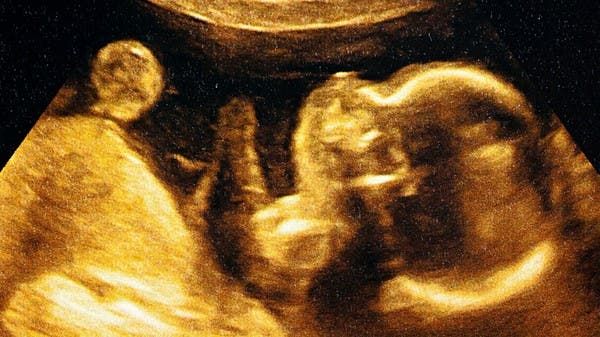

فقد توصلت دراسة جديدة إلى أن فحوصات الموجات فوق الصوتية مثل تلك المستخدمة لتتبع نمو الجنين يمكن أن تدمر خلايا المرض عن طريق إجبار سطحها على الانقسام والانفجار إلى الداخل، وذلك وفقا لما نشرته "ديلي ميل" البريطانية.